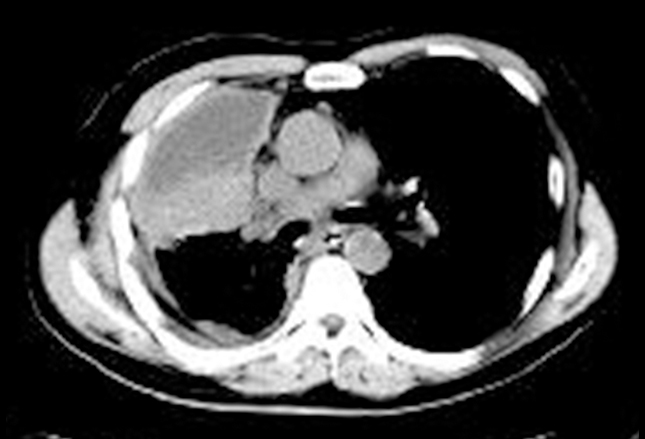

上图为SCLC患者的肺门CT扫描。右侧可见一个大的肺门肿瘤及肺膜增厚,提示胸膜转移。肿瘤组织周围可见局部肺积液,提示肺不张。